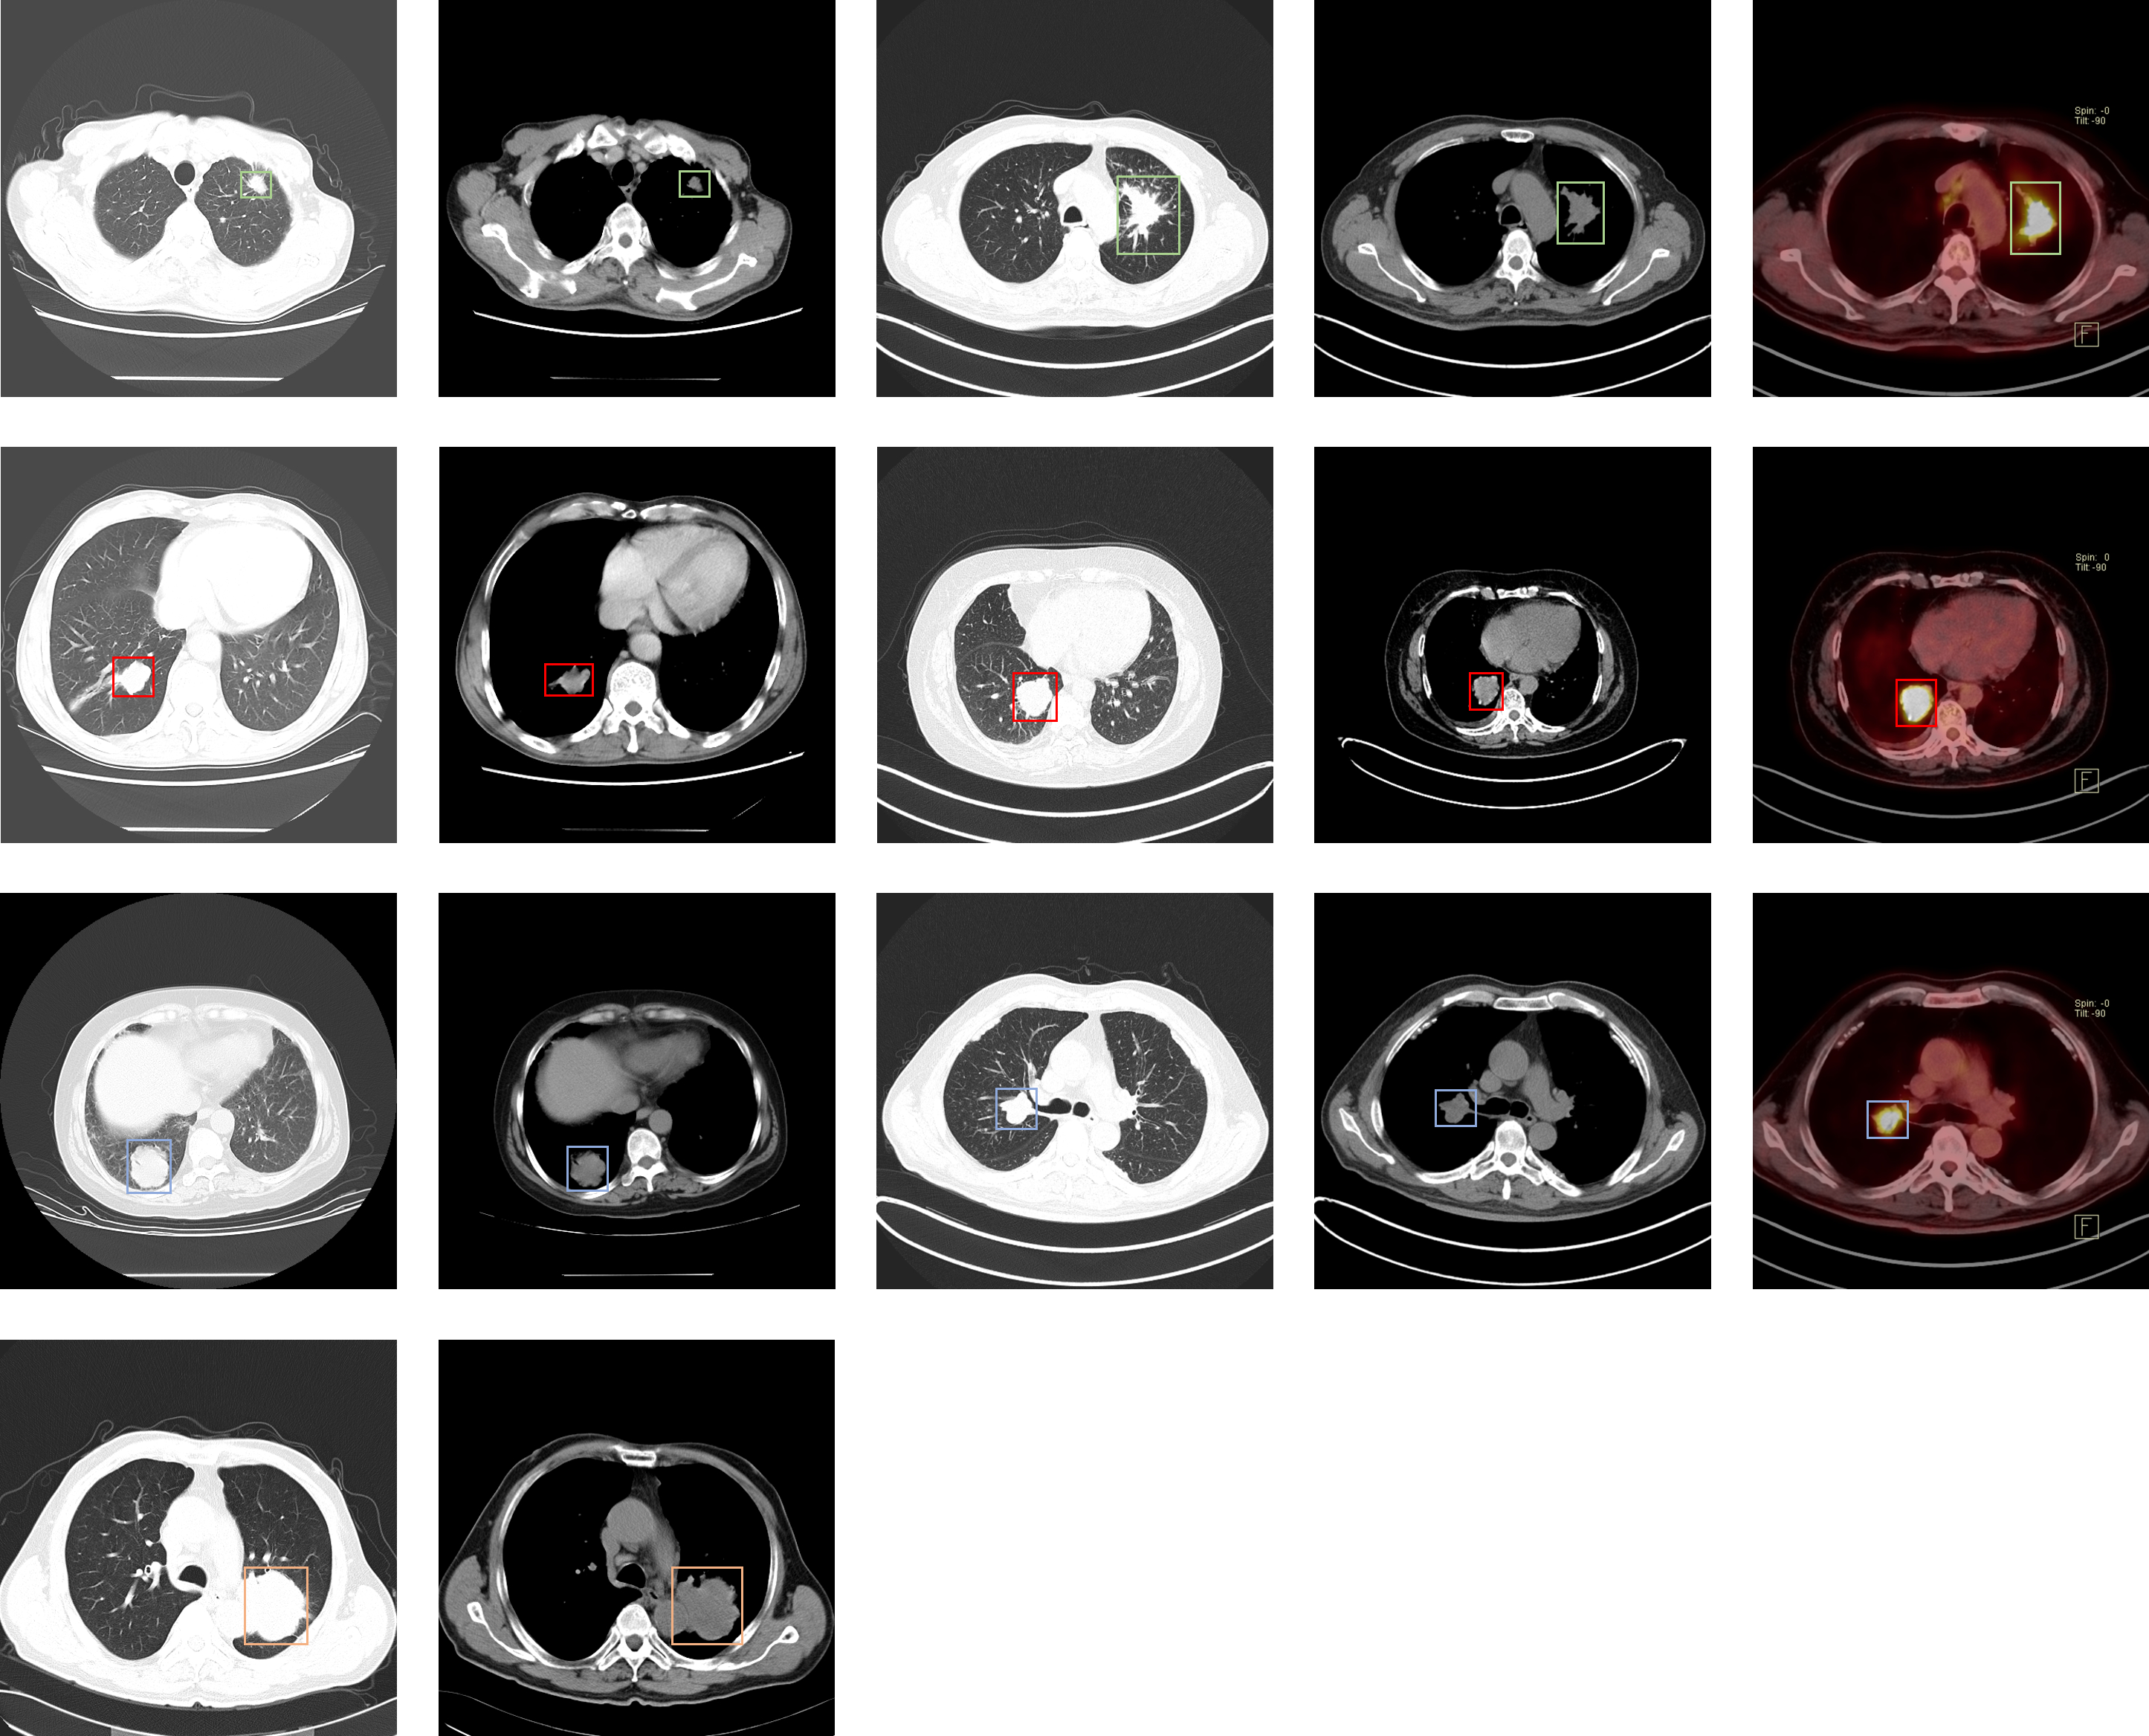

Lung-PET-CT-Dx

| Lung-PET-CT-Dx | 肺癌 | 目标检测 | CT | 363 | xml | dcm |

肺结节

| LIDC-IDRI | 肺部肿瘤 | 目标检测 | CT | 1012 | xls | dcm |

| LNDB | 直径大于3mm的肿瘤分割标注/小于3mm肿瘤和非肿瘤标记中心 | 分割/分类 | CT | 294 | XML | MetaImage |

介绍论文: LNDb: A Lung Nodule Database on Computed Tomography

| Lung Nodule Malignancy | 肺结界良恶性 | 分类 | CT | 4165+2526 | tif |